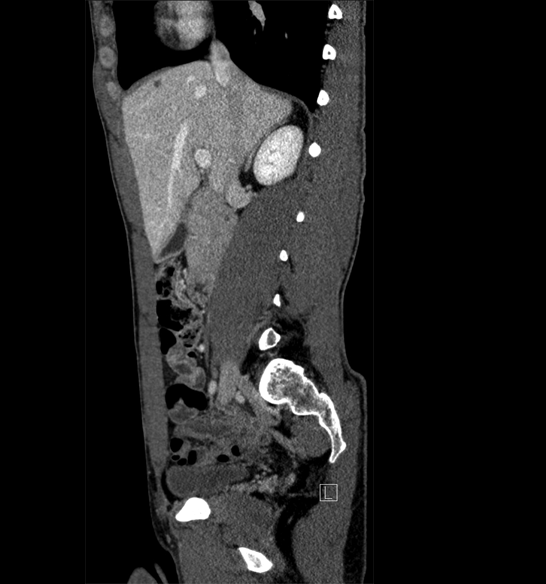

Body

Covers abdominal CT anatomy.